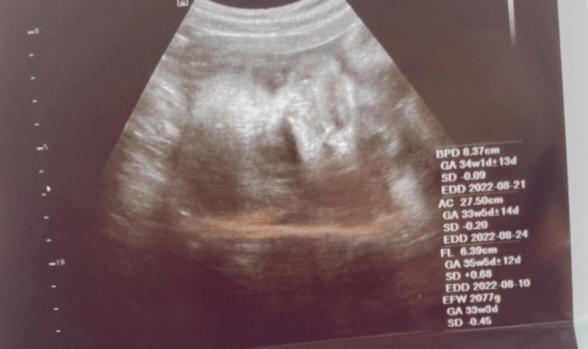

現在34週の妊婦です。今までもらったエコー写真を

整理して見返してたら胎児の鼻がちゃんと写ってなくて

鼻の骨がなかったり鼻が低いと生まれた時に異常があって産まれてくると聞いて心配になりました。

この写真から鼻に関して異常とか分かりますか?

赤ちゃんのお鼻がちゃんと写っていないということなのですが、お鼻の骨かなと思われるものは写っているように思いました。

異常になるのかどうかはわかりませんが、ちゃんとお鼻の骨はあるように思いました。

またかかりつけの先生にもご確認いただけたらと思います。